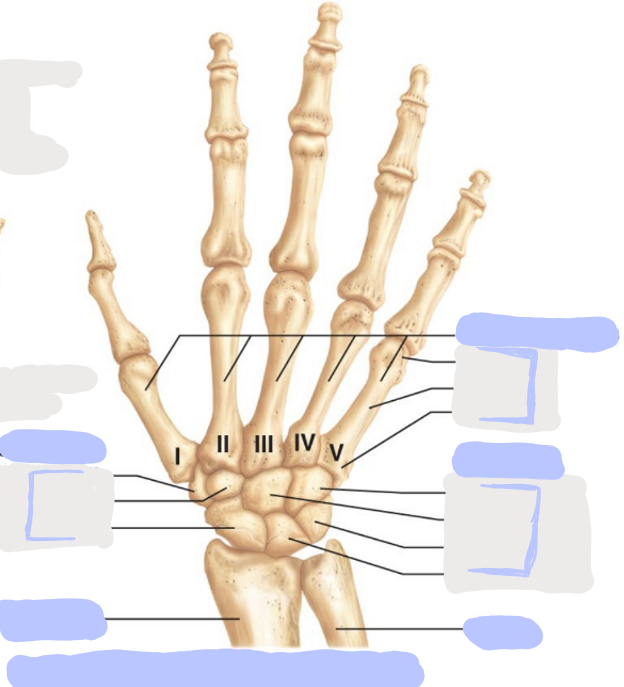

What is this picture of?

Posterior View of the Right Hand

What is here?

Where is the Ulna?

What is here?

Where is the Radius?

What is here?

Where are the Metacarpals?

What is here?

Where are some of the Carpals?

What is here?

Where are some of the Carpals?

How many carpals are there?

8

How many metacarpals are there?

5

How many phalanges are there?

14